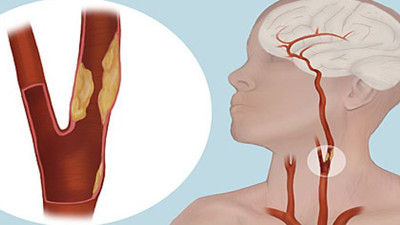

Tıkalı şah damarı kalıcı felcin habercisi mi? Oksijensizliğe sadece 3 dakika dayanabilen beyin ile ilgili sinyalleri bilmek, tedaviye hızlı erişim ile kalıcı felcin önüne geçerek hayat kurtarabiliyor.

Düzenli spor ve dengeli beslenme o tehlikeli hastalığı önlüyor Doç. Dr. Adnan Altun, beyne pıhtı atması hastalığının öncesi, sonrası ve tedavi aşamaları hakkında bilgi verdi.